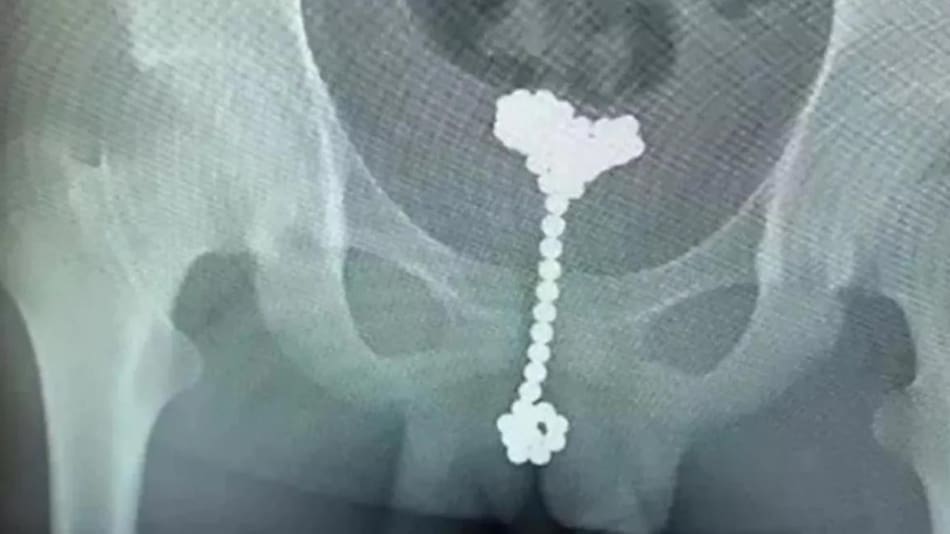

El juego de un nene de 12 años que quiso "experimentar" en su cuerpo, terminó con un problema gastrointestinal. Ocurrió en China, donde el menor le contó a sus padres que sentía molestias en la panza. Sin dudarlo, lo llevaron al hospital de niños Wuhan y allí se encontraron con el sorpresivo parte médico: encontraron 31 bolitas magnéticas en su pene.

Quedó al descubierto cuando los médicos le hicieron las radiografìas y vieron que estas esferas pertenecían a un juguete que está formado por pelotitas imantadas unidas entre ellas. Se usan para jugar y construir cualquier figura geométrica. Incluso, se sabe que los terapeutas las recomiendan porque desarrolla el ingenio y la psicomotricidad. Pero en este caso, el menor les dio otro uso.

El médico urólogo que lo atendió, Wang Jun, contó que se trató de un caso difícil porque las bolas eran pequeñas y se encontraban magnetizadas entre sí, lo que complicó la extracción porque se resbalaban al intentar quitarlas.

¿Cómo se las quitaron entonces? Llenaron la vejiga con aire para poder hacer la extracción sin que se movieran, de manera que se pudo evitar una operación más seria.